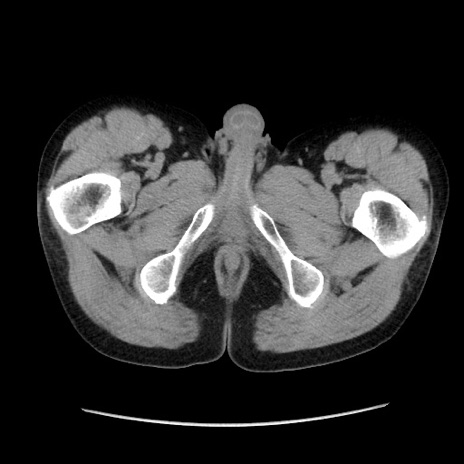

症例37(横断像)

【症例】40歳代 男性

【主訴】腹痛

【現病歴】4時間ほど前に電車に乗車中に臍部上より腹痛出現。徐々に増悪し起立困難となり、救急外来受診。生ものは数日食べていない。今朝お雑煮を食べた。

【身体所見】BT 36.8℃、BP 117/84mmHg、HR 91/min、SpO2 97%、苦悶様、腹部:臍上部広範囲圧痛あり、反跳痛±

【データ】WBC 8100、CRP 0.03